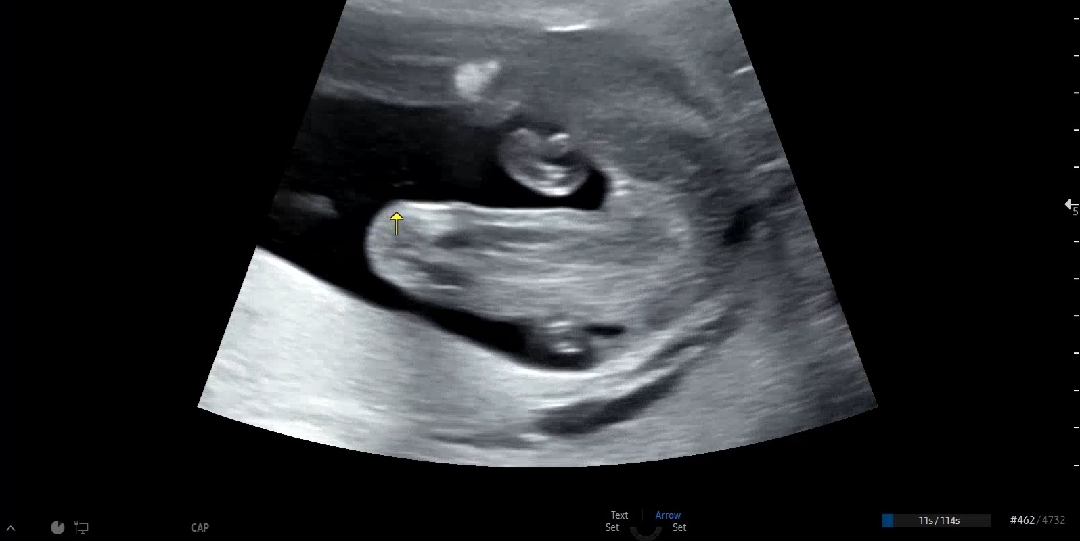

성별이 나왔는데 반전이 있을까요?

17주에 초음파로 확인했는데~ 성별 반전이 생기는건 아니겠죠? 걱정되네요~딸이라고 말씀하셨는데요

다행이네요~~ 진짜 아무것도 안보이더라구요

계속 딸같은데요?!

그쵸? 안바뀌겠죠^^